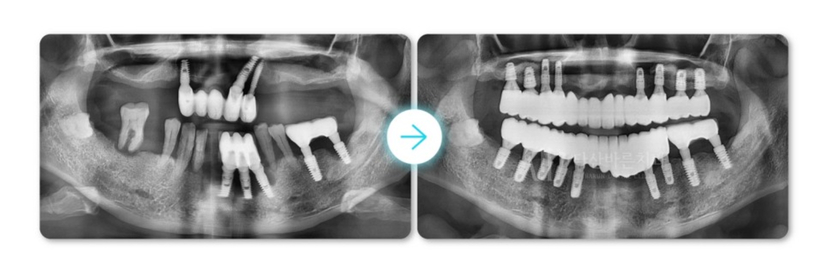

(Ảnh bên dưới) Đây là ảnh X-quang toàn cảnh được chụp sau khi bộ phận giả cấy ghép cuối cùng được hoàn thành.

Như đã giải thích ở trên, vùng răng cửa nơi xương hàm bị tiêu dần và yếu đi

đã được phục hồi bằng cách tái tạo lại xương nướu, nhưng không trồng lại trụ implant tại khu vực đó,

trụ implant lại được trồng vào vùng xương nướu khỏe mạnh xung quanh và kết nối với cầu răng.

Cấy ghép implant răng hàm bên trái được điều trị bằng phẫu thuật thẩm mỹ implant để ngăn ngừa mất xương hàm thêm.

Ở ảnh sau trên, răng cửa dưới nhìn khá dài nhưng nếu nhìn ảnh

thực tế bạn sẽ không có cảm giác như vậy chút nào.